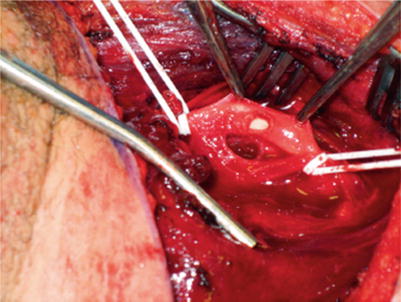

Fig. 29.2

Carotid injury

Once you divide the platysma and retract the SCM laterally, your next objective is to identify the internal jugular (IJ) vein and retract it laterally with a self-retraining blunt retractor. The facial vein usually needs to be ligated and divided to allow the IJ to retract laterally. Often there is a pseudoaneurysm/hematoma encountered at this point; however, if the hematoma remains intact, it is helpful to dissect alongside the hematoma in order to gain control of either proximal or distal vessels. Depending upon the position of the hematoma, you may only be able to obtain control of one or the other prior to invading the pseudoaneurysm. It is unlikely that you will be able to do both prior to opening the hematoma, but if possible certainly gaining both proximal and distal control is ideal. I prefer to gain control with vessel loops vs. vascular clamps in the neck, as the vessel loops are less traumatic to a soft, healthy carotid artery (Fig. 29.2).

Once the most proximal or distal control is obtained, then continuing your dissection to the center of the problem is the next step. You will need to apply digital pressure as the pseudoaneurysm is entered to allow you to evacuate clot and gain better proximal and distal control.